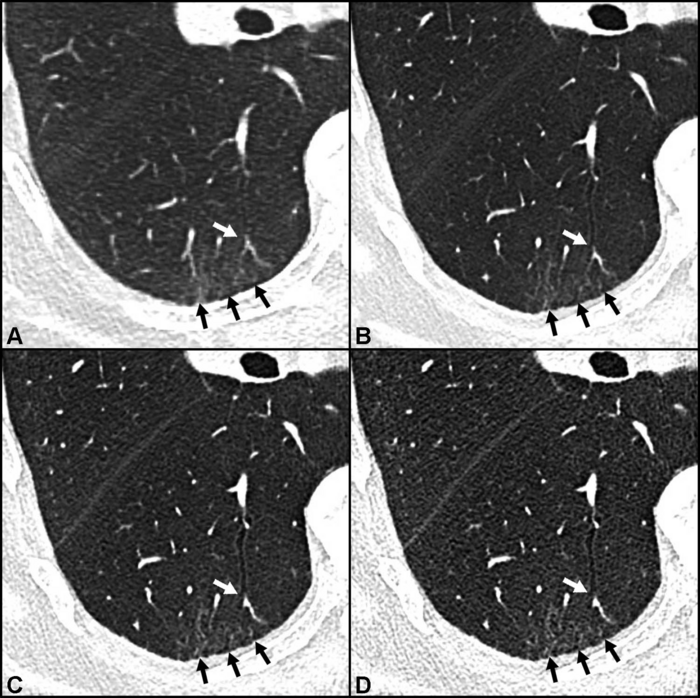

Conventional CT showed post-COVID-19 lung abnormalities in 15 of 20 (75%) participants. PCD CT revealed additional lung abnormalities in half of the participants. The most common abnormality found by PCD CT was bronchiolectasis, damage to the airways that can cause difficulties in clearing mucus from the lungs.

“In our study investigating lung abnormalities in symptomatic post-COVID patients, we were able to detect subtle lung abnormalities in 10 of 20 participants using PCD CT that were not seen in conventional CT,” Dr. Heidinger said. “Moreover, PCD CT has potential in decreasing radiation dose and in artifact reduction, representing direct benefits to patients.”

PCD CT’s ability to detect these subtle lung abnormalities is especially important, Dr. Heidinger said, because patients with persistent symptoms following COVID-19 can develop irreversible lung damage known as lung fibrosis. Conventional CT is one of the primary methods for detecting and diagnosing lung fibrosis, but it can miss the subtle abnormalities indicative of early-stage fibrosis.